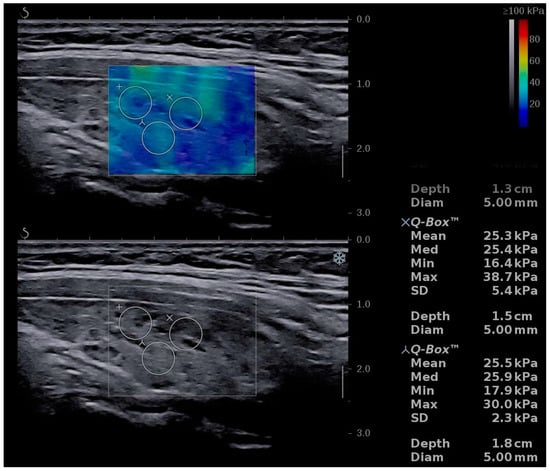

| Mean TS values | 15.51 ± 4.76 | 10.41 ± 2.01 | p < 0.0001 |

| Left lobe mean values | 15.46 ± 4.77 | 10.32 ± 2.22 | p < 0.0001 |

| Right lobe mean values | 15.56 ± 5.22 | 10.50 ± 2.14 | p < 0.0001 |